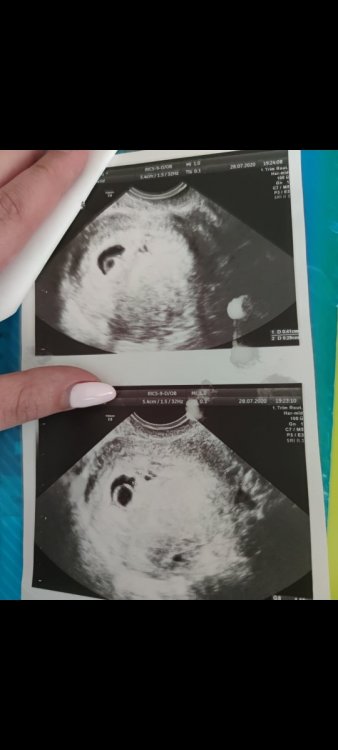

U mnie w pierwszej ciąży w 7tc5d był taki obraz usg. Ciałko żółte za duże w stosunku do pęcherzyka. A u Ciebie zupełnie inaczej to wygląda.

Screenshot_2021-06-22-14-39-50-169_com.miui.gallery.jpg

U mnie twierdzi że za mało urosło od poprzedniego tygodnia. Nie wiem może ja  się nie znam ale na  moje to urosło. Nie wiem czy konsultować to z innym lekarzem czy czekać na bete czy co robić.